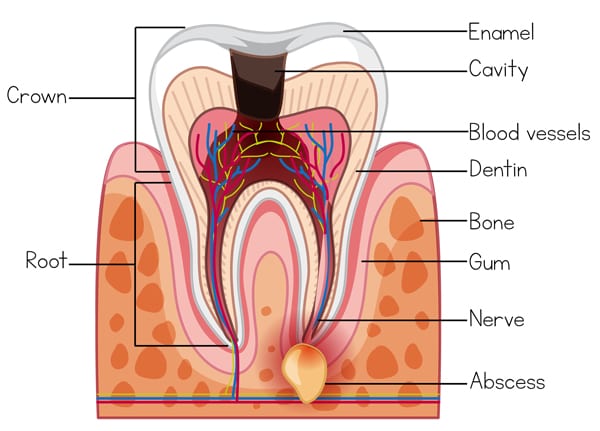

The root of a tooth is the soft tissue that lives inside every tooth (also known as the “dental pulp”), which contains nerves and blood vessels that help keep the tooth alive and healthy.

These blood vessels extend from the pulp of the tooth to the end of the tooth through the root canals.

The dental pulp can become inflamed due to decay or injury, which typically leads to revere episodes of toothaches. An infection tooth can lead to the surrounding bone and gums as well, causing further complications.

Pulp tissue within a tooth contains blood vessels and nerves. When the pulp matter within the tooth becomes infected or inflamed, a root canal treatment is required to prevent further infection. The most common cause of pulp inflammation or infection are cracked tooth, severe cavities or other serious injury to the tooth. These are the few ways that bacteria can enter the tooth and infect the pulp.